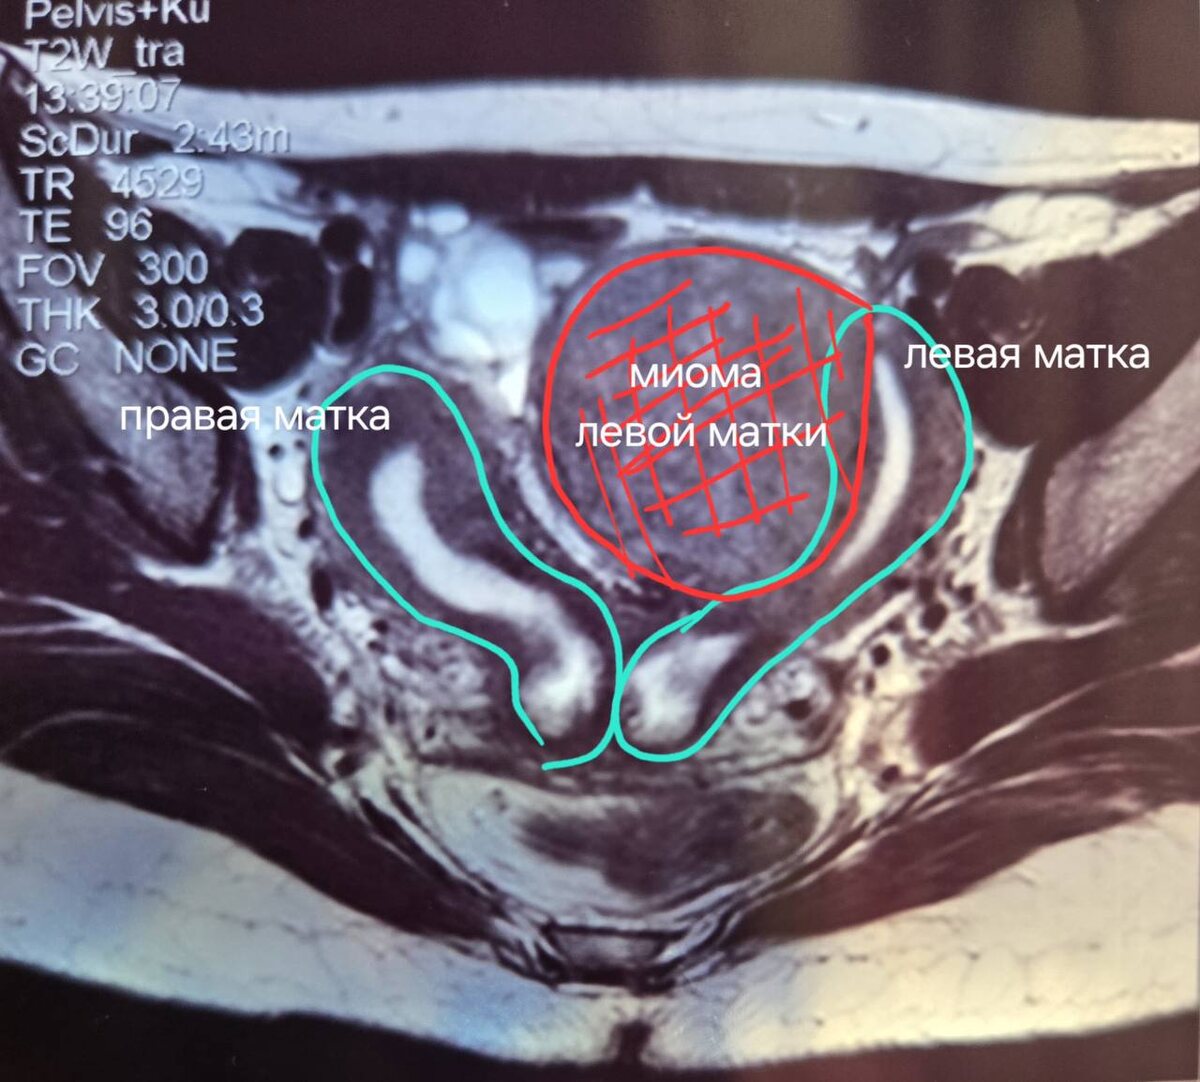

В Ростове-на-Дону врачи обнаружили у пациентки необычную аномалию - у девушки было два влагалища и две матки.

Пациентка пришла на прием 25 сентября. Она безуспешно пыталась забеременеть. Причиной тому стало довольно редкое отклонение — у пациентки было две матки, две шейки-матки и два влагалища. О своей особенности она узнала несколько лет назад.

- Полное удвоение матки и влагалища относится к редким врождённым порокам развития. Распространённость этой аномалии — 2 случая на 10 тысяч женщин, - отметил Олег Дробин.